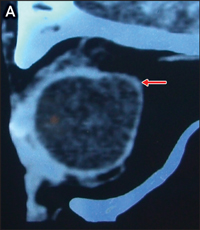

In 2008, an 88-year-old woman with a background of well controlled systemic hypertension and high myopia presented to an emergency department with a 5-day history of left periorbital swelling, erythema and mild discomfort, without visual loss. She was seen in the ophthalmology clinic on the same day. Her visual acuity was 6/12 in each eye. She was afebrile, with left upper and lower lid erythema, oedema closing the palpebral fissure, and conjunctival and scleral injection. Slit-lamp biomicroscopy revealed normal anterior chambers; clear, well centred intraocular lens implants from previous uncomplicated cataract surgery; and posterior staphylomata (an incidental finding of bulging of the globe seen in some highly myopic patients). A computed tomography (CT) scan revealed left periorbital soft tissue thickening, with stranding confined to the preseptal area (Figure A). Radiologically, the patient appeared to have periorbital cellulitis, although clinical examination, being more sensitive to ocular signs, revealed postorbital septal spread of infection as evidenced by scleral injection (not expected to be seen on a CT scan), leading to the diagnosis of orbital cellulitis. Intravenous antibiotics were administered for 3 days, with moderate resolution of the periorbital swelling, although the scleral injection remained.

A: Sagittal computed tomography scan showing left periorbital soft tissue thickening and posterior staphyloma. |